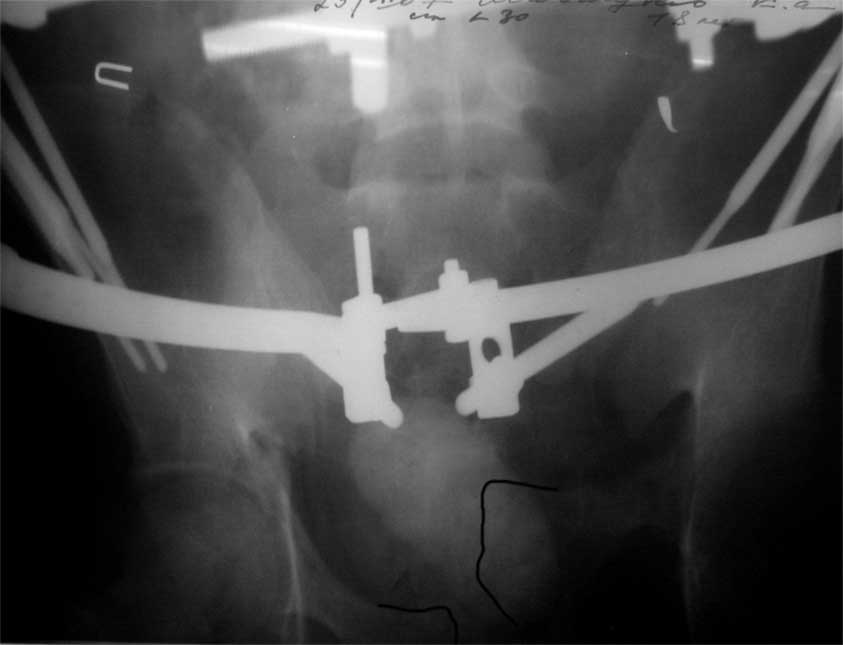

продолжение темы. не увидел энтузиазма в обсуждении. Вопросы прежние, первым этапом закрыто устранили вертикальное и передне-заднее смещение. Каким образом восстановить целостность тазового кольца, из каких доступов? Снимки в приложении